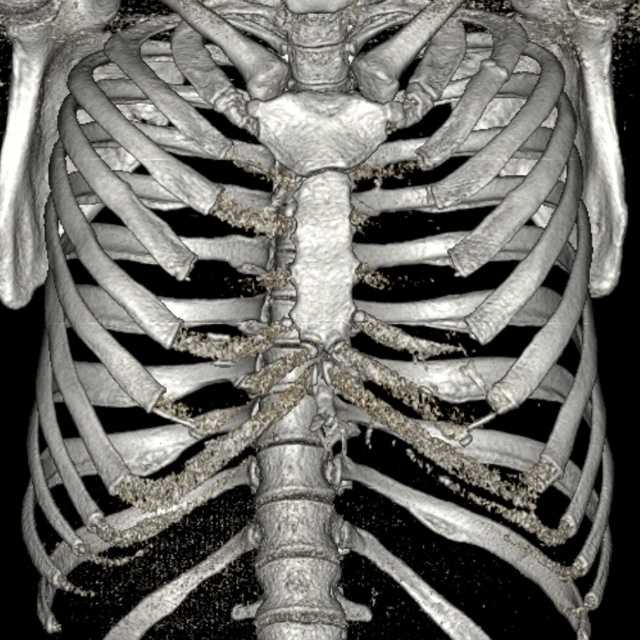

Повторная расшифровка КТ показывает МЕТАСТАЗЫ В РЕБРАХ при аденокарциноме прямой кишки

Компьютерная томография (КТ) грудной полости

Травма органов грудной клетки на примере клинических случаев